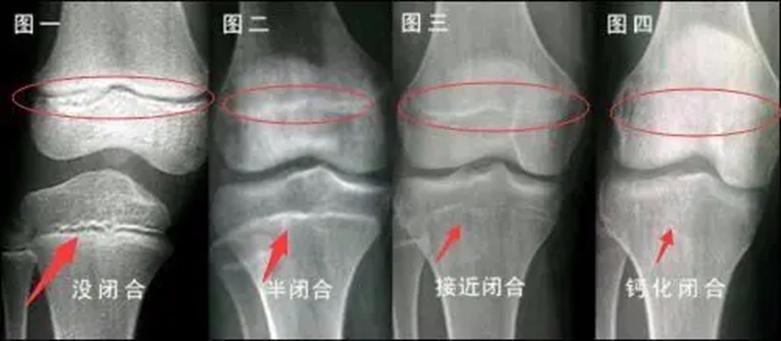

人全身的发育状况可以从骨骼发育中窥见一斑,骨骼的发育又与骨骺的形态有着密切的联系。骨骺有四个生长阶段: 生发期、增殖期、塑形期以及闭合期 ,骨骺的发育受到很多因素的影响,但是生长阶段不会因为骨的发育而有所提前。所以可以 从骨骺的生长时期情况判断骨是否还在生长。

骨骺线闭合过程示意图 来源 | 百度百科